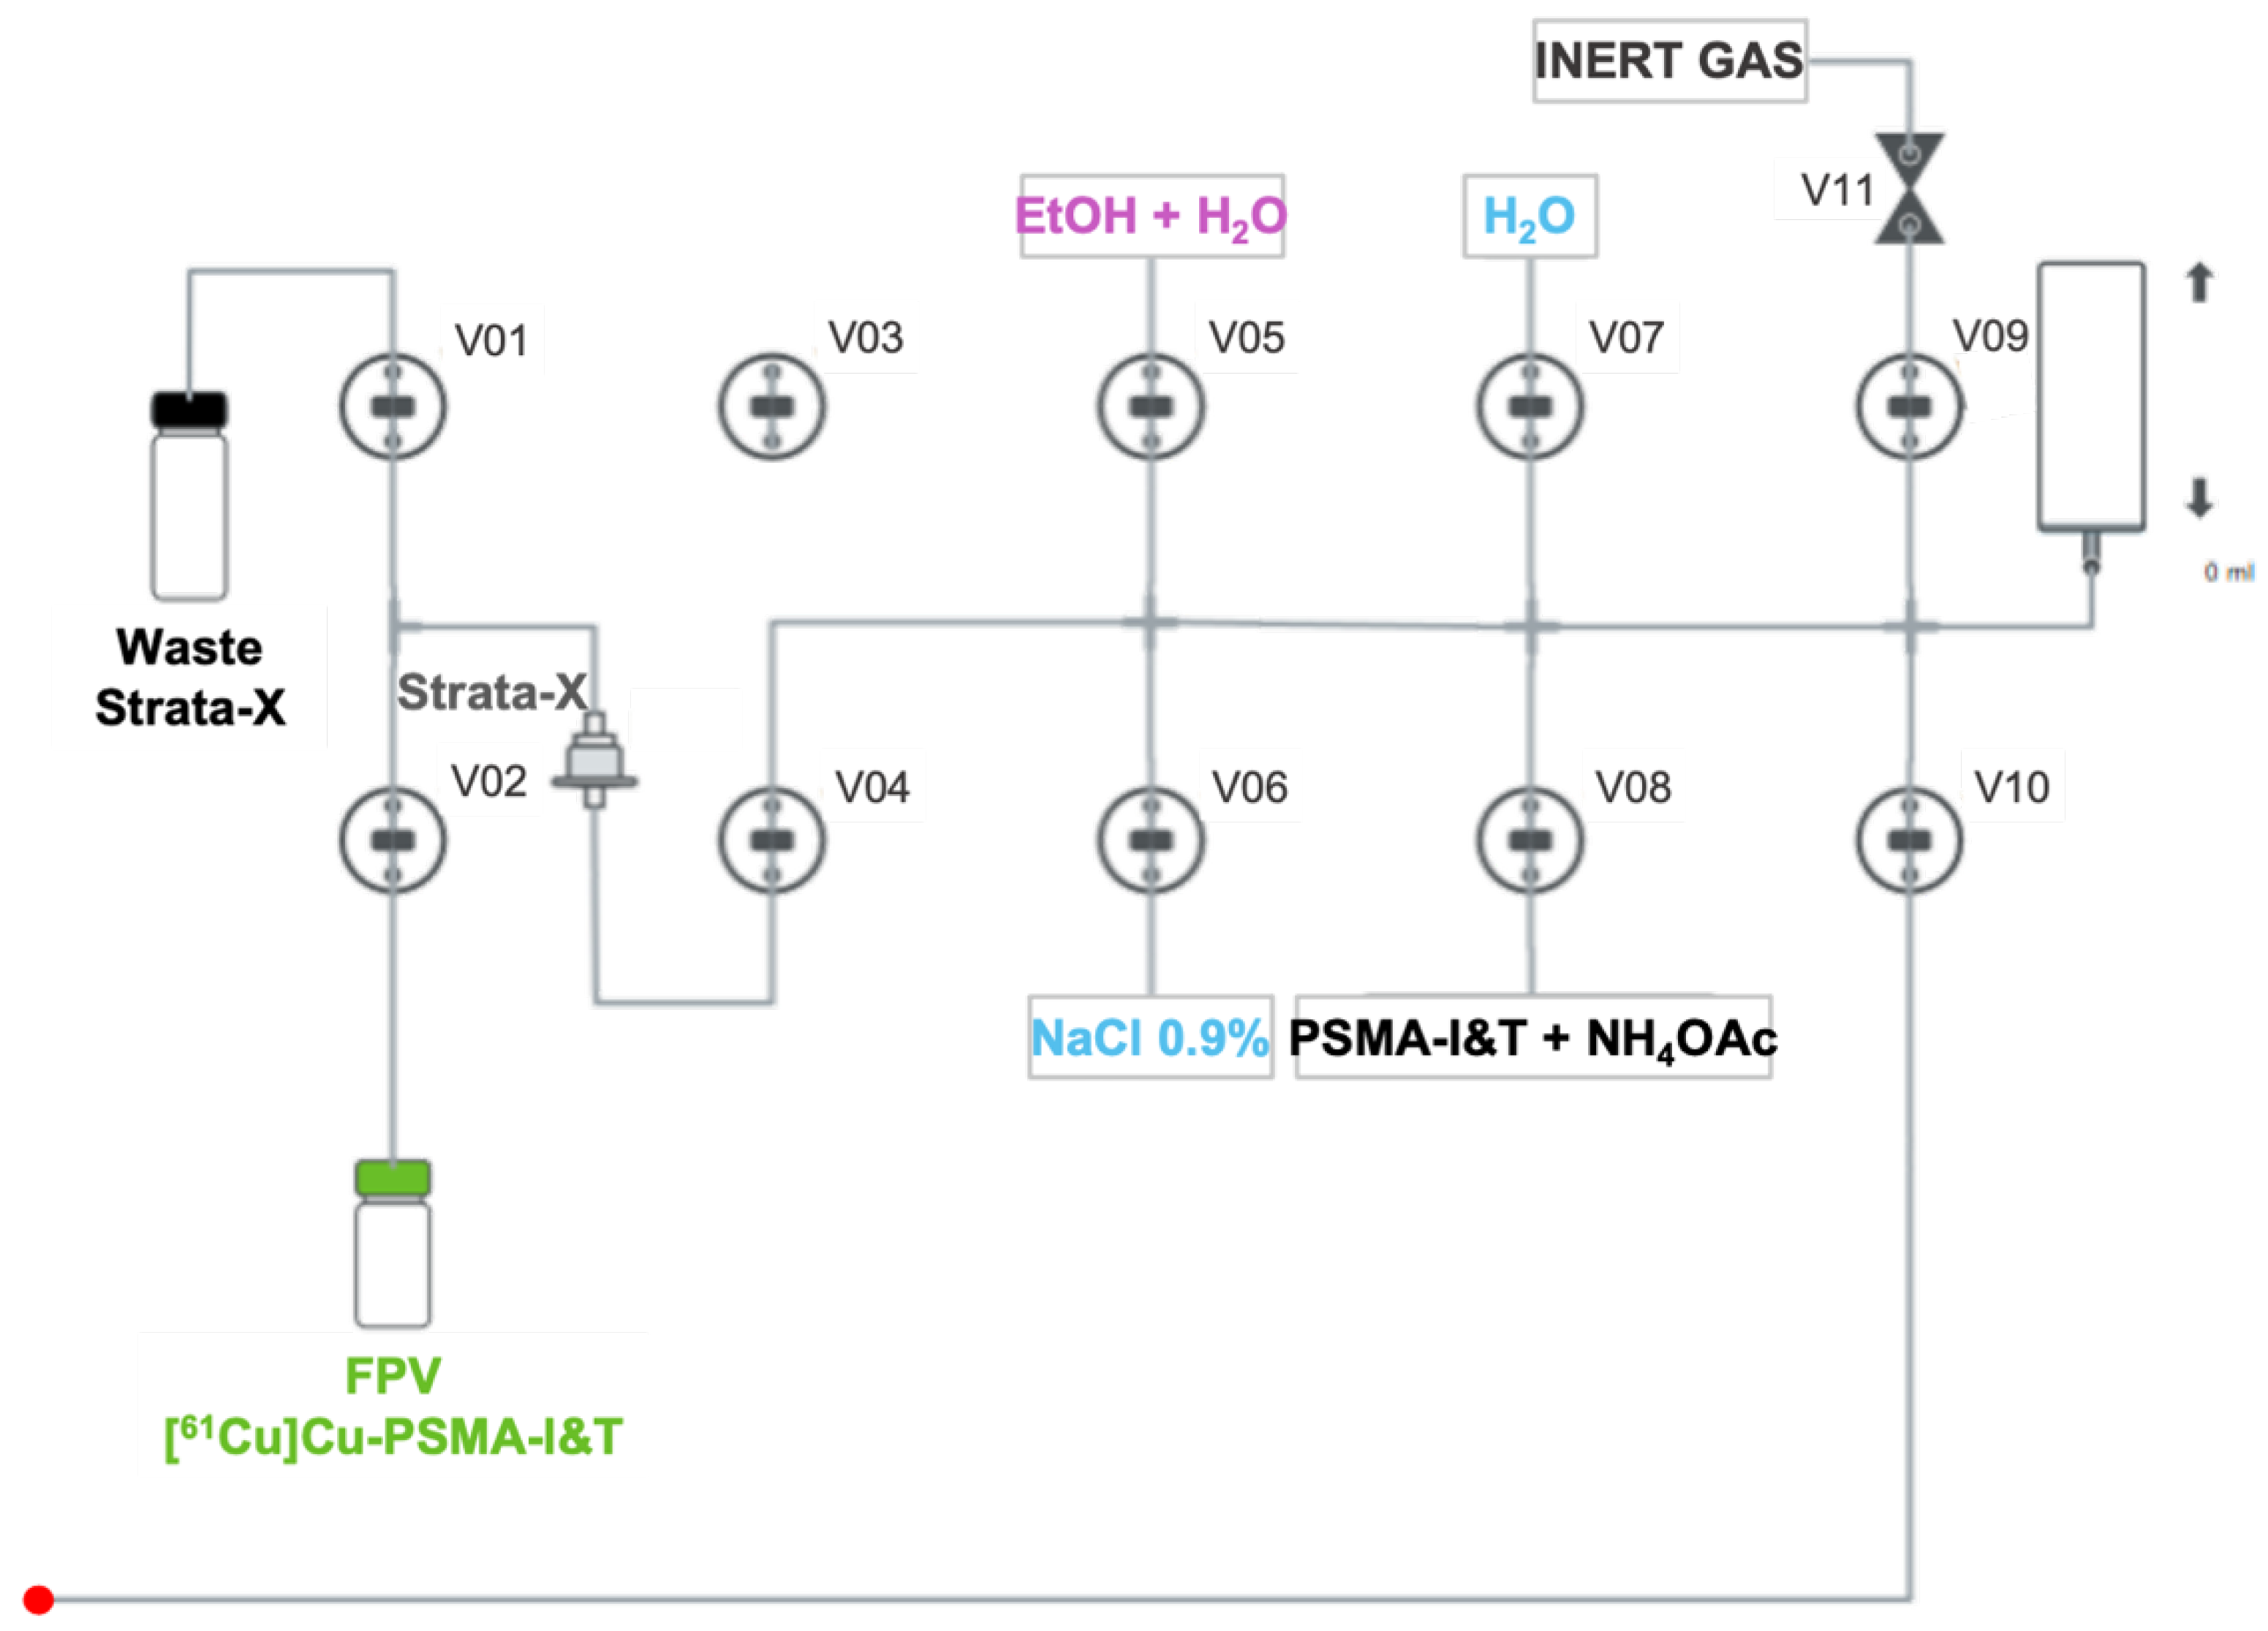

4.2. Automated Synthesis of PSMA-Based Radiopharmaceuticals

- A mass of 30 µg of DOTAGA/NODAGA-PSMA-I&T diluted in 5 mL of NH4OAc 2 M is transferred to the reaction vial (Figure 6) and mixed with [61Cu]CuCl2;

- The radiolabeling reaction occurs for 10 min at 100 °C with pH fixed between 3.5- 4.5;

- After that time, the reaction mixture is diluted with water (5 mL) and passed through a Strata-X cartridge into the waste container to remove free copper-61;

- The Strata-X cartridge is rinsed with water (5 mL) and eluted with 2 mL of a water/EtOH solution (1:1) into the FPV;

- Finally, 8 mL of NaCl 0.9% is added to the FPV in order to get the radiopharmaceutical in its injectable final formulation.